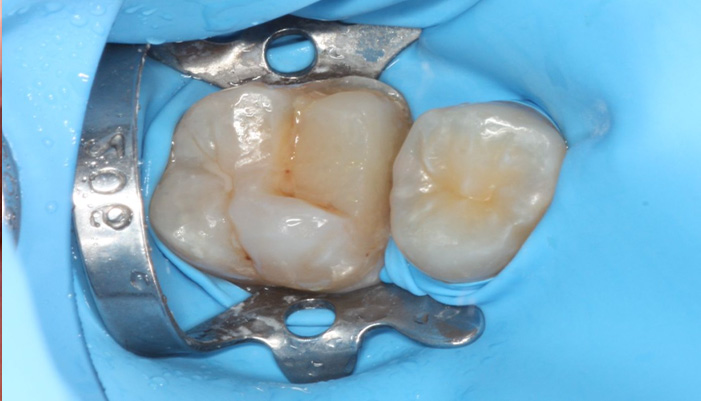

症例3

治療前

治療後

治療の経緯

患者様は「インプラントした部分を長く安心して使える状態にしたい」とのご希望で来院されました。初診時は、すでにインプラントが埋入されており二次手術前の状態でしたが、角化歯肉の幅が不足しており、将来的な清掃性や安定性に不安がある状態でした。そこで、単純な二次手術のみではなく、インプラント周囲に十分な角化歯肉を確保する処置を併用し、清掃しやすく長期的に安定しやすい環境を整えました。

同じ症状で悩んでいる方への

メッセージ

インプラント治療は「入れること」がゴールではなく、その後も長く安定して使い続けられることが重要です。歯ぐきの状態や清掃のしやすさまで考慮することで、トラブルの予防につながります。インプラント後の違和感や不安がある方も、ぜひ一度ご相談ください。

| 主訴 | インプラント治療の続き。 |

|---|---|

| 治療期間 | 1回 |

| 治療費 | ¥33,000(税込) |

| 治療内容 | インプラントの2次手術として歯肉形成を行いました。硬いしっかりした歯茎(角化歯肉)がないと将来的にインプラントが炎症を起こしやすいためです。 |

| 治療のリスク | 腫れ・出血などが生じる場合があります。 |